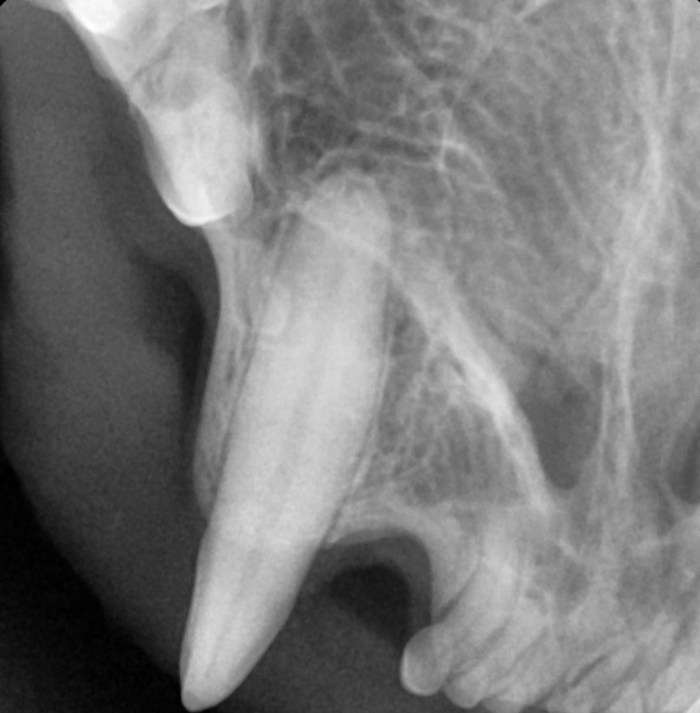

병원에서는 기본 영양 수액과 마취 전 피검사, 엑스레이 촬영을 진행했습니다. 고양이를 동물병원에 맡기고 5시간 후, 엑스레이 결과가 나왔습니다. 상태는 예상보다 심각했으며, 보이지 않는 곳까지 치아가 녹아버린 상황이었습니다. 멀쩡한 치아는 양쪽 어금니 하나씩과 앞니 위에 4개, 아래에 2개뿐이었습니다. 치아흡수성병변은 재발 가능성이 80%에 달하며, 문제성 치아를 모두 발치하더라도 치아 교합이 맞지 않아 전발치도 고려해야 한다는 설명을 들었습니다. 만일 전발치를 하지 않고 초기증상 발생한 치아까지만 발치한다면 내년에 또 재발할지도 모른다는 설명이 있었습니다.